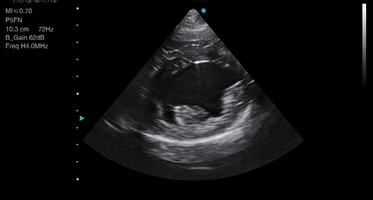

How to use your ultrasound machine - 7 tips for vets

At first glance, vet ultrasound machines can appear complicated and the sheer number of buttons, kno...

10 min read